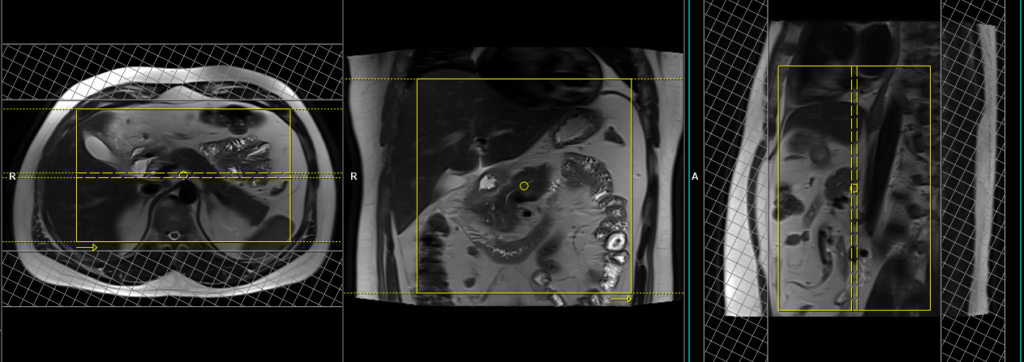

Small FOV T2 tse\HASTE breath hold 3mm

Plan the axial slices on the coronal breath-hold images and position the block horizontally across the abdomen as shown. Verify the positioning in the other two planes. Establish an appropriate angle in the sagittal plane, aligning it horizontally across the abdomen. The slices must be sufficient to cover the entire pancreas, starting one inch above the pancreatic tail and extending down to the C loop of the duodenum. The phase direction should be from right to left to minimize ghosting artifacts from the anterior abdominal wall. Use phase oversampling to prevent wrap-around artifacts. Consider adding saturation bands at the top and bottom of the block to minimize artifacts caused by fat signal, arterial pulsation, and breathing. Instruct the patient to hold their breath during image acquisition.

Note:Scans achieve better results when performed with a right-to-left phase direction and 70% oversampling. This choice is made to prevent artifacts caused by motion of the abdominal wall fat. However, in most scanners, implementing this option is not feasible due to the additional oversampling, which would extend the breath-hold time beyond what patients can manage. As a result, we conduct the scan with an anterior-posterior phase direction on our 1.5T scanner and right-to-left on our 3T scanner. If TSE images exhibit excessive artifacts, consider utilizing a HASTE sequence.

Parameters

TR 4000-5000 | TE 90 | FLIP 150 | NEX 1 | SLICE 3MM | MATRIX 256×224 | FOV 250 | PHASE A>P | OVERSAMPLE 30% | IPAT ON |